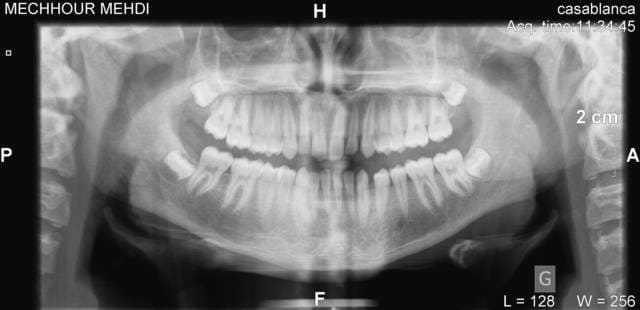

J'ai suivi cette discussion depuis le debut et il manque un element essentiel que personne n'a demande! A l'examen clinique y a-t-il vraiment cette laterdeviation vraie? Sur la radio panoramique (je n'ai pas reussi a faire copier-coller ici), avec la tige entre les incisives et le proglissement de la mandibule on ne trouve plus cette deviation!!! et cela veut propabelemet dire que la deviation est plutot fonctionnelle que reelle. Sur la cephalo on trouve aussi un decalage au niveau des condyles sans avoir le meme decalage au niveau des cavites glenoides ce qui confirme partiellement mon hypothese. L'element le plus tranchant ici c'est l'examen clinique et en cas de doute il faut peut etre monter le cas sur articulateur avec un arc facial et recherche de la RC afin de traiter le cas a partir des rapports dentaires en RC et non pas en PIM. Sans ces precisions et des reponses a mes questions je trouve il est completement abberant de poser un plan de traitement.

Voici un essai pour mieux voir en sachant que la radio panoramique n'est pas le meilleur document pour une telle evaluation. A vous de juger.

--

A suivre...

Said

Tu as fait ta mesure de symétrie maxillaire/mandibule sur la panoramique qui est une radio prise en bout à bout incisives, cela enlève toute sa valeur.,